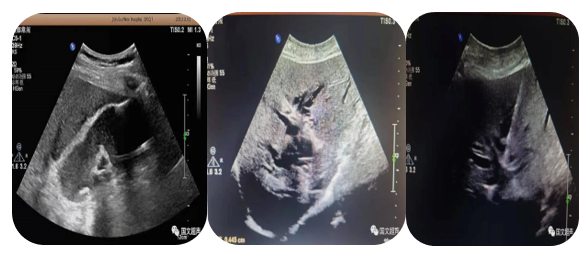

4.超声介导下肝占位射频及微波消融术

通过射频电极发出高频率射频电流,电能使局部组织发生正负离子震荡,并摩擦生热达100°左右,热能逐渐传导至周围组织,形成一个预定的球形或类球形的消融区,肿瘤局部因高温而发生凝固坏死。以达到和手术切除同样的目的和效果。

5.超声介导下囊肿硬化治疗

局部麻醉患者清醒状态超声直视下穿刺针进入囊肿囊腔内抽出囊液,注入硬化剂,手术时间短,损伤轻微,痛苦小,安全性高。